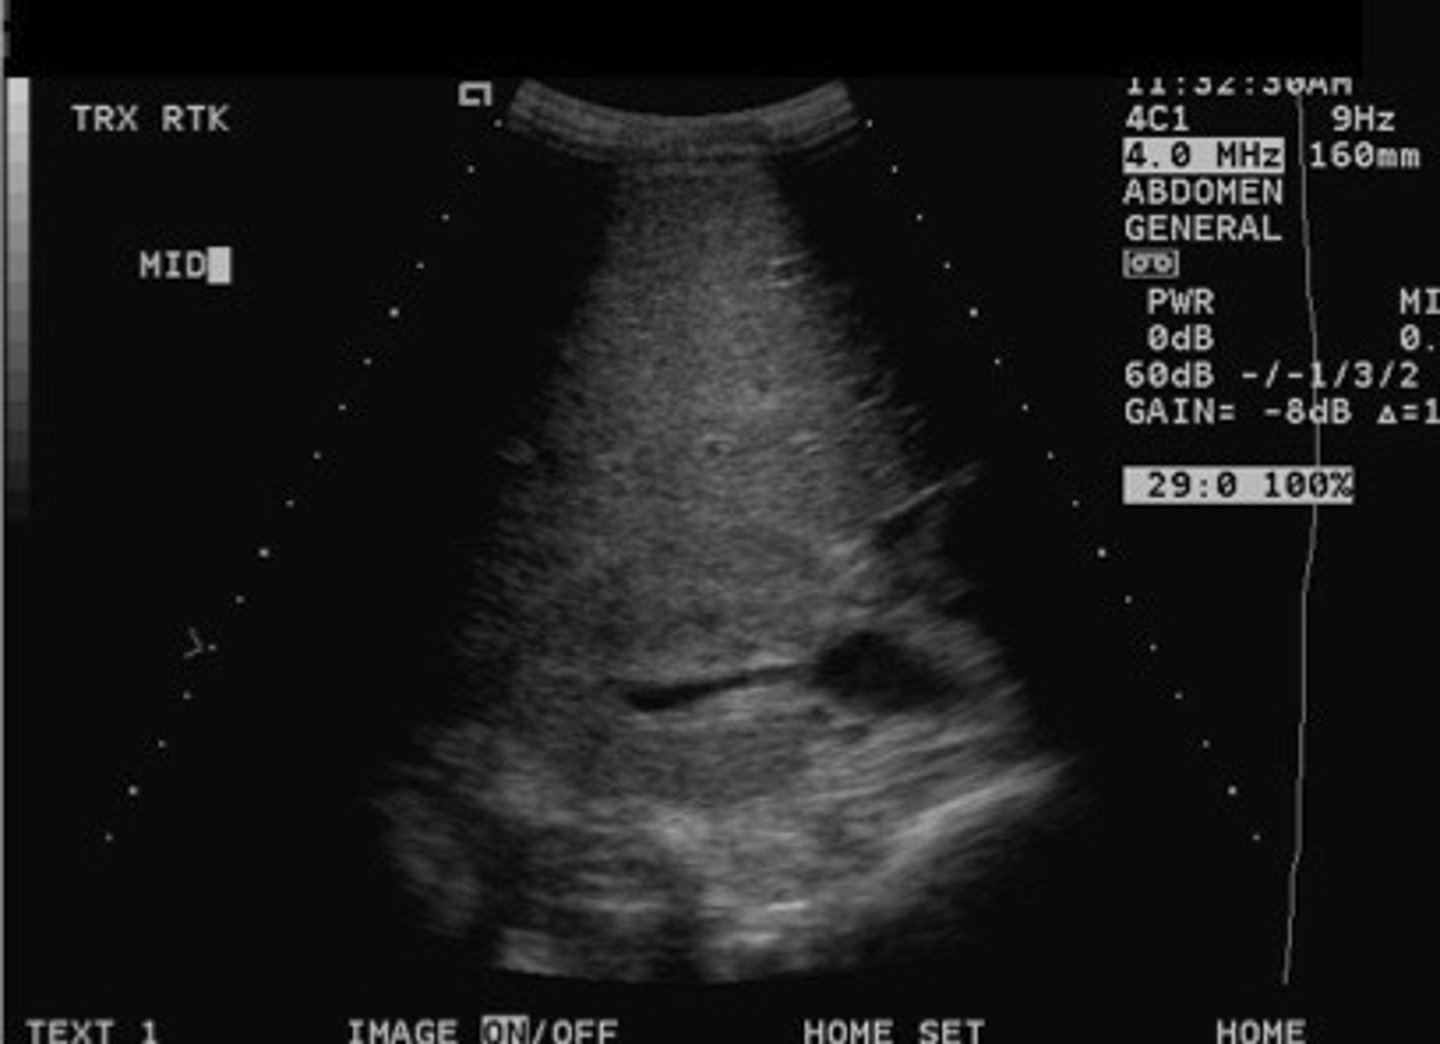

Stone difficult to identify in the sinus region

What does this image show

<p>What does this image show</p>